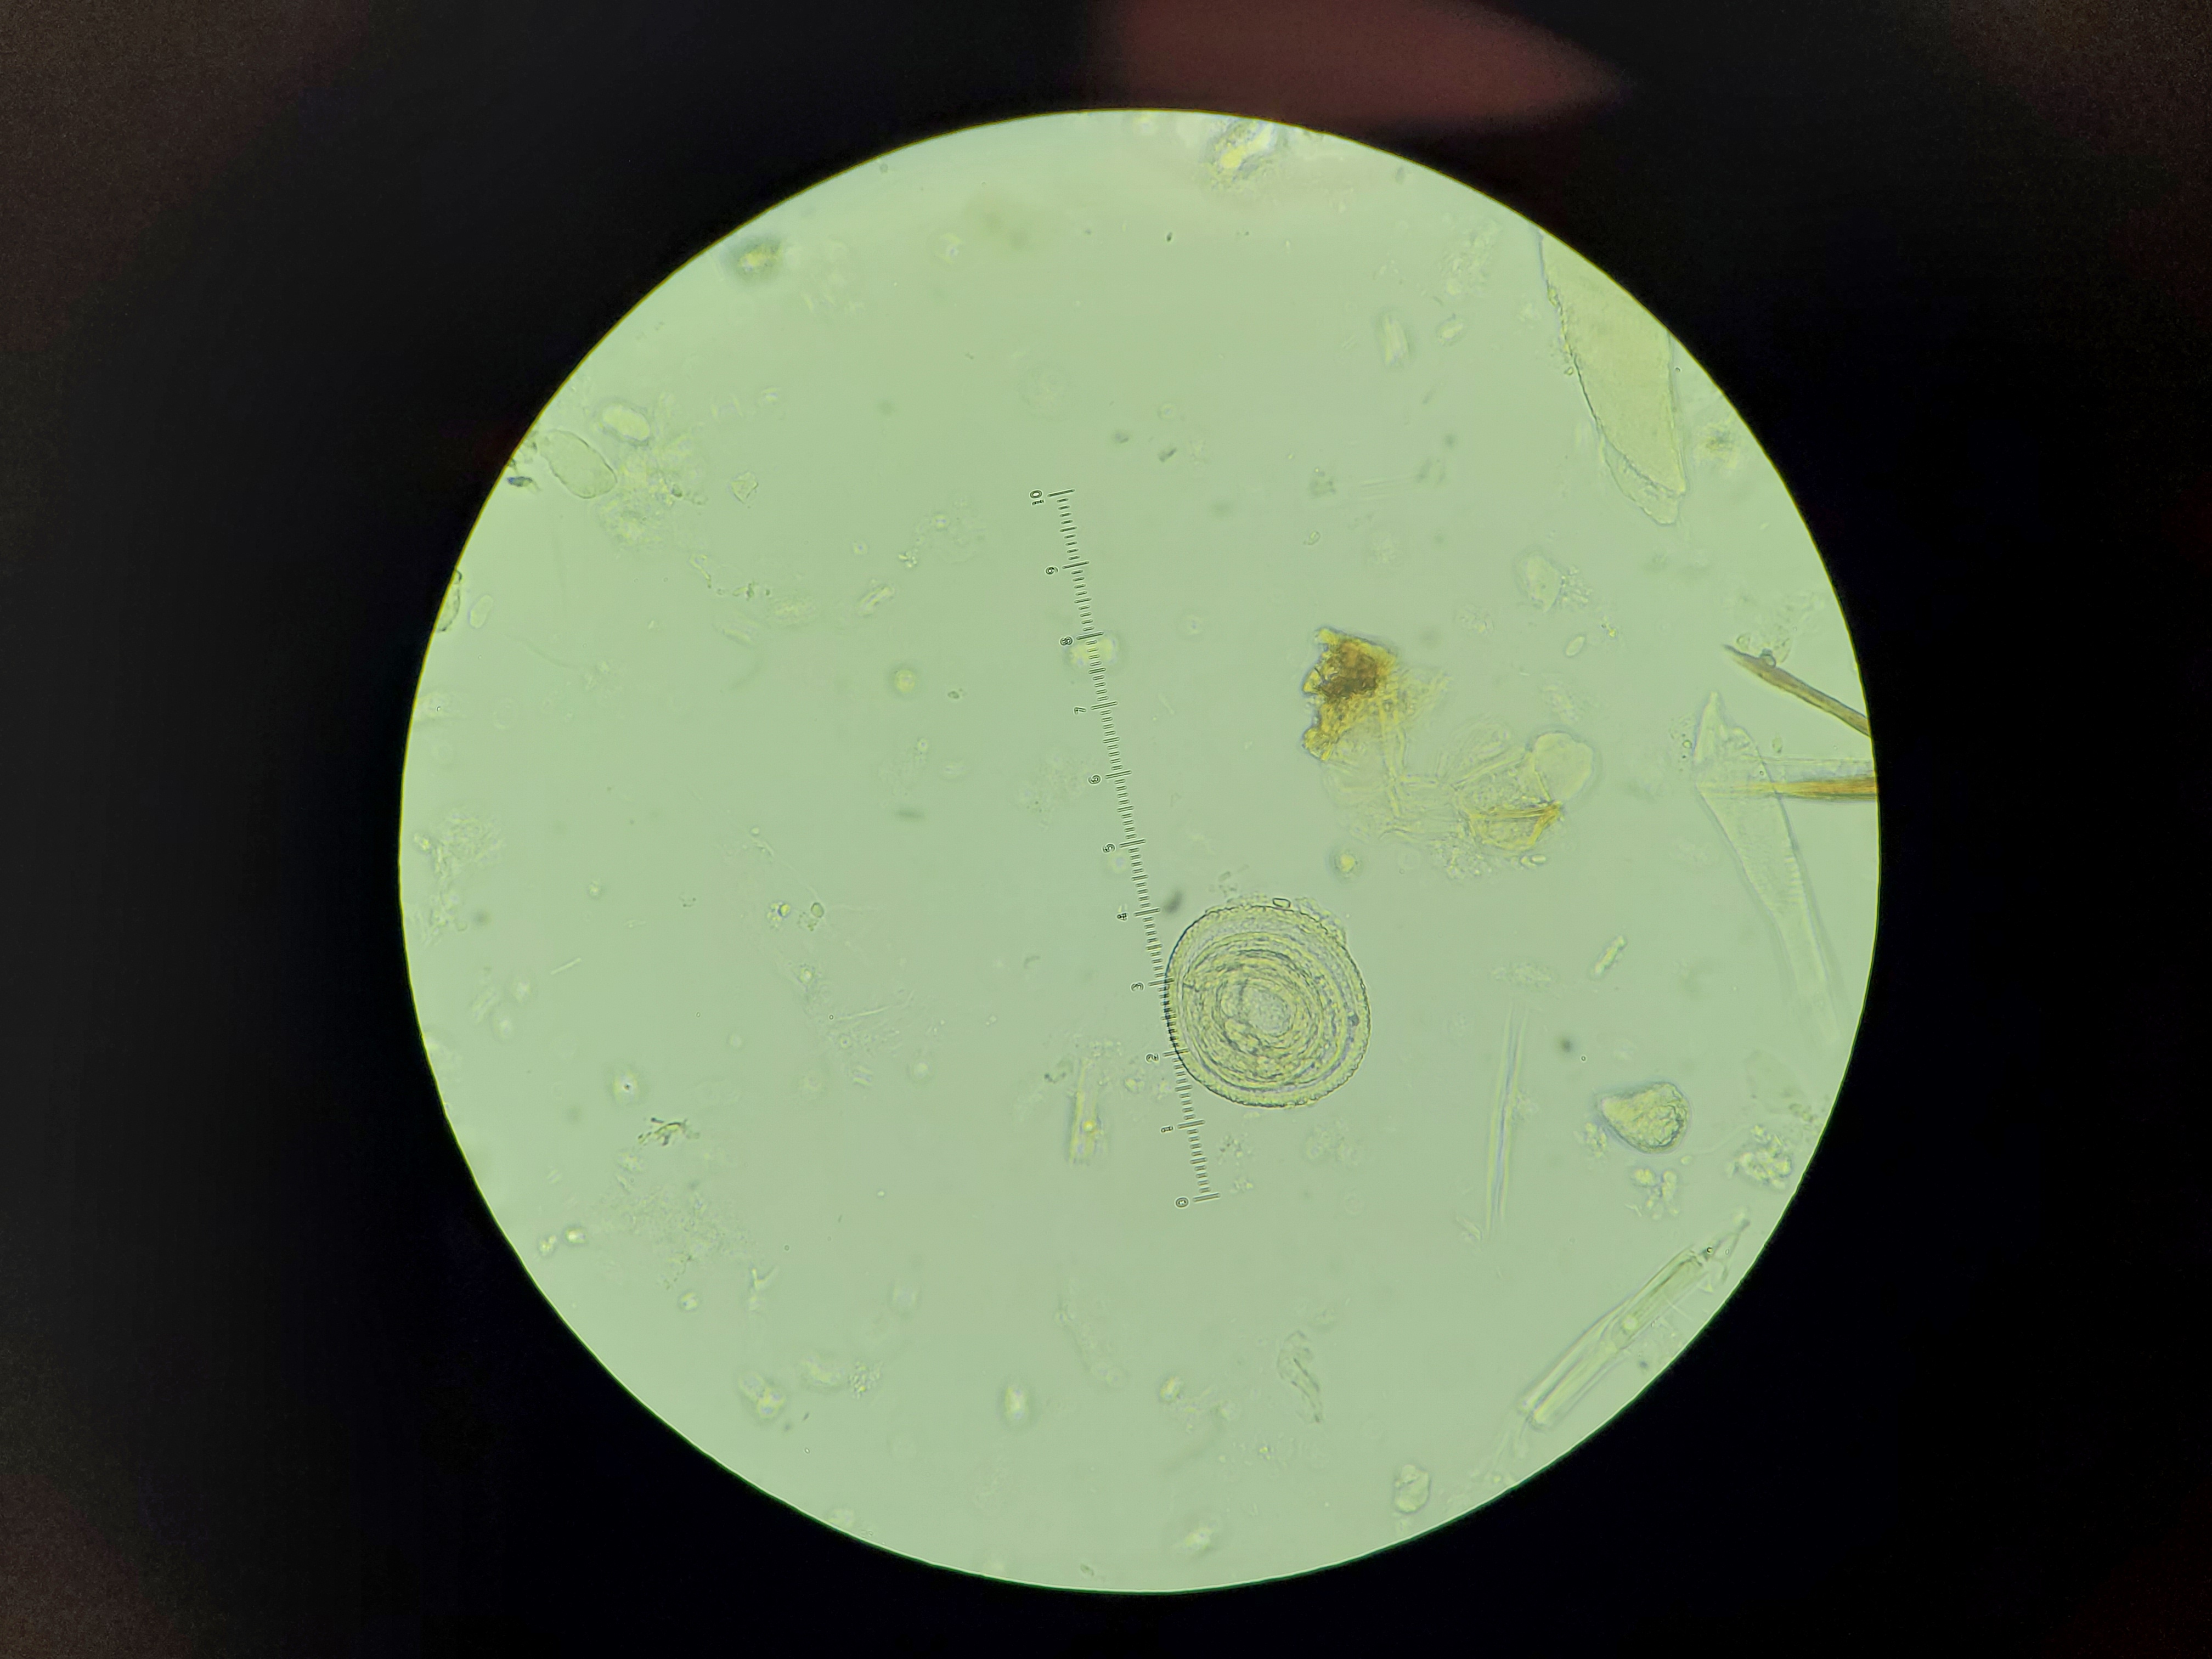

Trichinella spiralis

Stage: Larvea